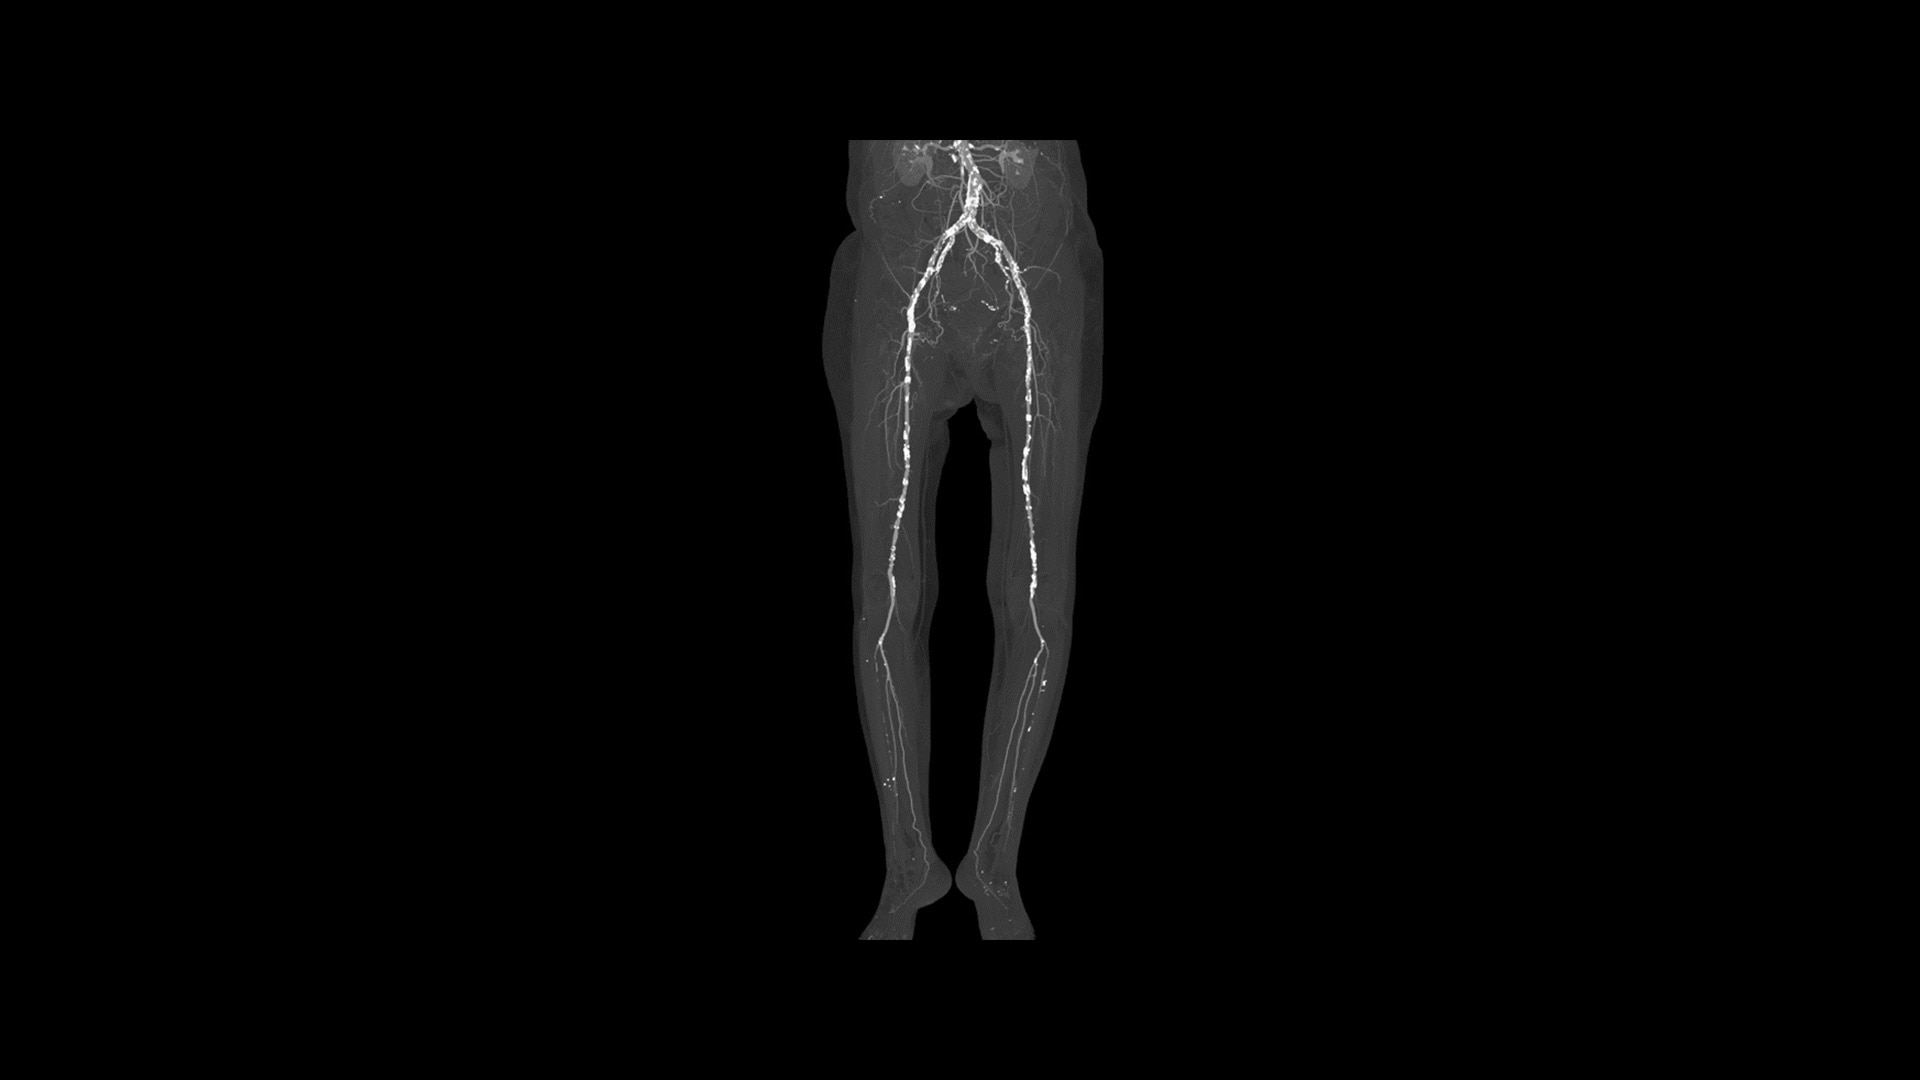

True Enhance DL

Designed to enhance what matters

True Enhance DL is a deep learning-based processing method intended for contrast enhancement of single energy images. True Enhance DL uses a dedicated Deep Neural Network (DNN) trained to estimate monochromatic, 50 keV GSI images from single-energy X-ray. This technology brings four deep learning models that the user can choose depending on different contrast enhancement phases by clinical tasks.

feature-hero-true-enhance-dl-desktop